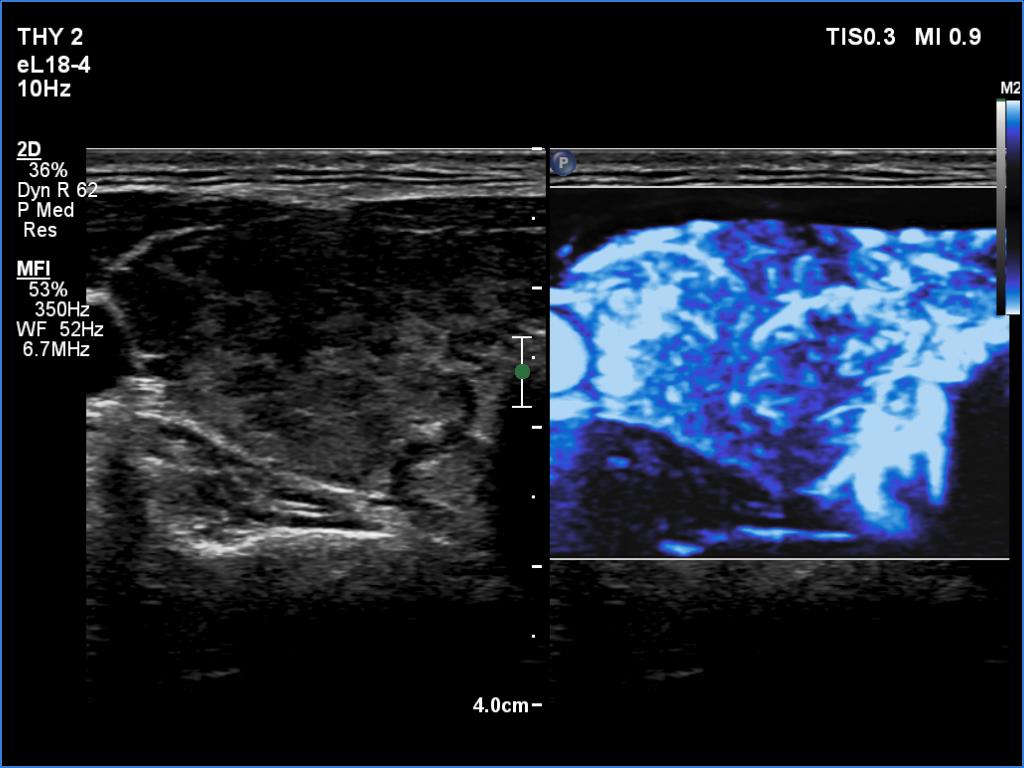

Right lobe, microflow imaging

Left lobe, microflow imaging